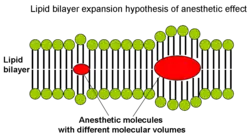

From the correlation between lipid solubility and anaesthetic potency, both Meyer and Overton had surmised a unitary mechanism of general anaesthesia. They assumed that solubilization of lipophilic general anaesthetic in lipid bilayer of the neuron causes its malfunction and anaesthetic effect when critical concentration of anaesthetic is reached. Later in 1973 Miller and Smith suggested the critical volume hypothesis also called lipid bilayer expansion hypothesis.[21] They assumed that bulky and hydrophobic anaesthetic molecules accumulate inside the hydrophobic (or lipophilic) regions of neuronal lipid membrane causing its distortion and expansion (thickening) due to volume displacement. Accumulation of critical amounts of anaesthetic causes membrane thickening sufficient to reversibly alter function of membrane ion channels thus providing anaesthetic effect. Actual chemical structure of the anaesthetic agent per se is not important, but its molecular volume plays the major role: the more space within membrane is occupied by anaesthetic - the greater is the anaesthetic effect. Based on this theory, in 1954 Mullins suggested that the Meyer-Overton correlation with potency can be improved if molecular volumes of anaesthetic molecules are taken into account.[22] This theory existed for over 60 years and was supported by experimental fact that increases in atmospheric pressure reverse anaesthetic effect (pressure reversal effect).[21][23][24]

Then other, physicochemical theories of anaesthetic action emerged that took into account the diverse chemical nature of general anaesthetics and suggested that anaesthetic effect is exerted through some perturbation of the lipid bilayer.[25] Several types of bilayer perturbations were proposed to cause anaesthetic effect, including (1) changes in phase separation, (2) changes in bilayer thickness, (3) changes in order parameters, or (4) changes in curvature elasticity.[26][27][28]